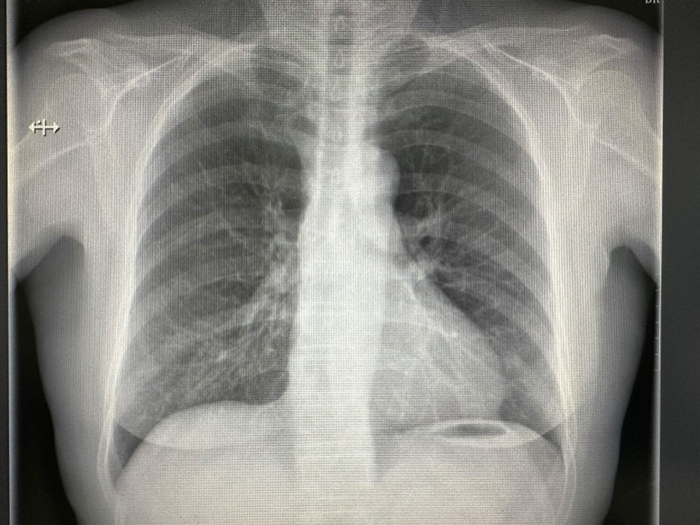

小知识5:既然CT更清楚,为什么不一开始就做CT?这是因为对于诊断不明确的初步筛查,临床首选是普通X光平片检查,一是辐射剂量低,二是更符合筛查流程。对于普通X光平片检查不能确诊的,再进一步行CT。对于常规胸部检查来说,一次胸部CT的辐射剂量大约等于200张普通X光胸片的辐射剂量。虽然CT的辐射剂量比普通X光平片大,但是对于肋骨骨折的明确诊断,CT对于发现肋骨骨折的能力是普通X光平片的2倍。根据国家发布的《X射线计算机断层摄影成年人诊断参考水平》,人体各部位做CT检查时,承受的辐射量为: